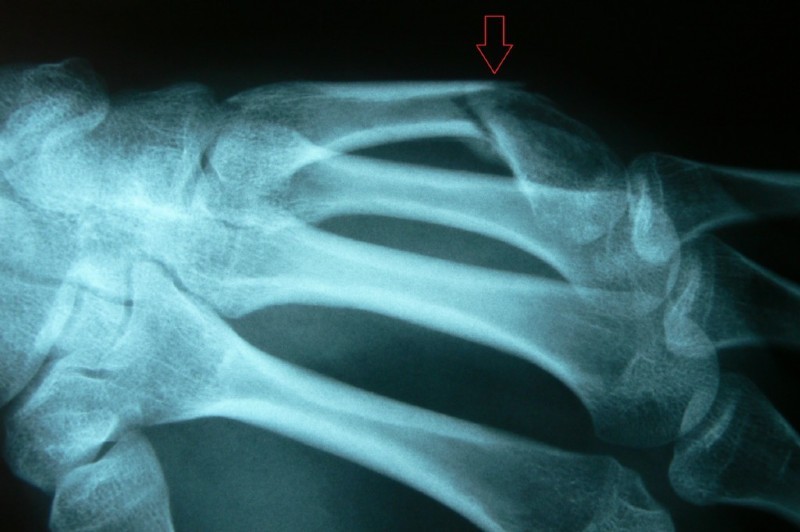

Fracture of the hamate bone

The young man (boxer) punched aggressively and once felt a sharp pain in the wrist.